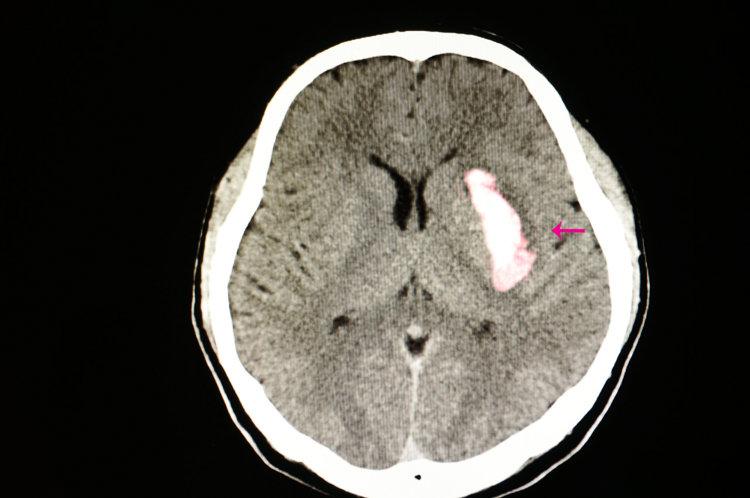

南方醫科大學中西醫結合醫院神經醫學中心兼神經外科陳陸馗主任介紹:腦出血也稱爲“腦溢血”,是指非創傷導致的腦內血管破裂,腦實質內聚集血液,在腦卒中中佔比25%—55%。據統計,每年每十萬人中有12—15人出現腦出血,發病一個月的死亡率可高達35%—52%

腦出血的發生主要是因爲腦血管病變血管出現硬化、彈性變差,這個時候受劇烈血壓波動影響,血管就可能出現破裂出血。

如果腦出血發生在大腦半球,出血量超過30毫升,那就可能危及生命;如果腦出血發生在小腦、腦幹、後顱窩等部位,出血量超過10毫升,可能會危及性命;如果腦出血發生在腦幹重要部位,那出血量只有5毫升,也可能會致命。